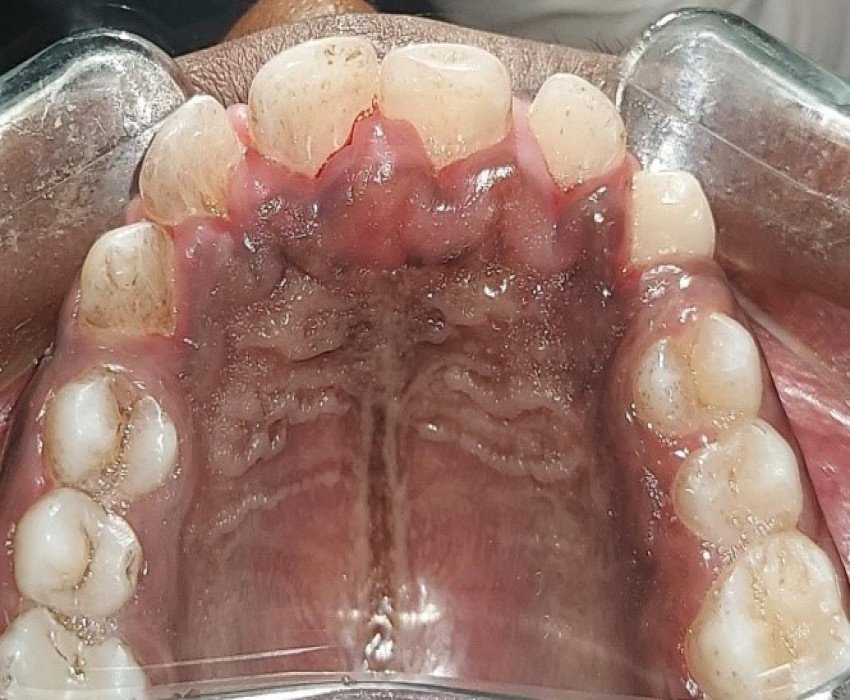

A 15-year-old male patient reported to the Department of Pedodontics, Saraswati dental college, Lucknow, Uttar Pradesh, India with a chief complaint of localized gingival enlargement in the upper anterior teeth region since last 9-10 months.

Idiopathic gingival enlargement with hyperpigmentation

- Gingivectomy, Depigmentation with Laser